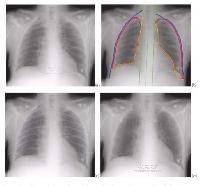

Изучение проблемы низкого качества рентгенограмм на Вашем оборудовании.

Мобильный рентгенаппарат + оцифровщик. Получение рентгеновского изображения на экране ноутбука. Вариант за 1,4 миллиона рублей под ключ.

Мобильный рентгенаппарат с печатью рентгенограмм на рентгеновской пленке. Цена 700000 рублей.